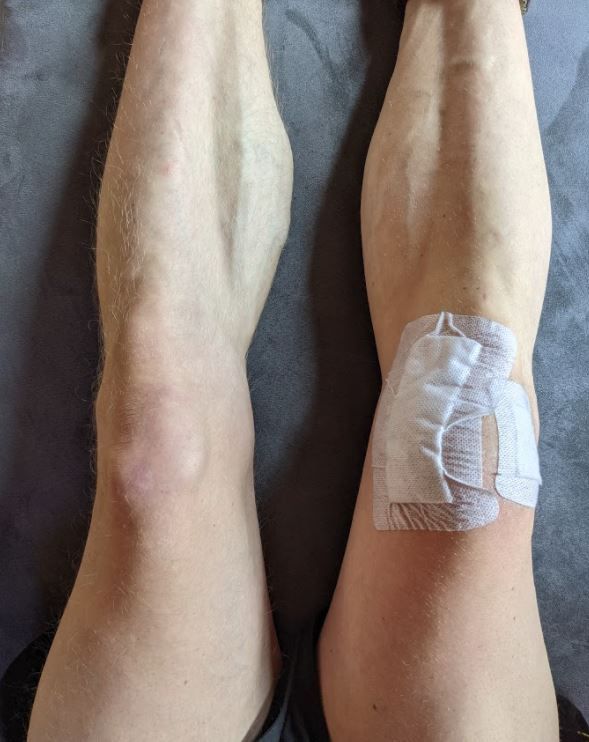

Zwei Monate sind nun seit der zweiten Arthroskopie vergangen - und da demnächst noch einmal wieder eine Reihe weiterer "Ideen" ansteht, soll der Zeitpunkt gekommen sein, vor diesen ein Update zu hinterlassen. Besser geworden ist leider so gut wie gar nichts - ich wüsste nicht, was ich über die zweite Arthroskopie Positives verlieren sollte. Mir ist zwar augenscheinlich ein Narbenstrang medial im Hoffa abhanden geraten, sprich entfernt worden, aber dieser scheint nicht weiter relevant gewesen zu sein (oder...letzte vage Hoffnung...hat den Hoffa so lange genervt, dass dieser jetzt Monate braucht, um sich wieder zu berappeln). Das Knie...die Zyste:

Knie mit Bakerzyste.JPG

Mit Symptomen fange ich gar nicht erst weiter im Detail an. Als "Beweis" für den persistenten Reizzustand genügt mir tagtäglich der genervte Blick auf meiner Bakerzyste, bei der ich heute einmal wieder das Gefühl hatte, mich einer weiteren Ruptur (dann #5 oder 6, was weiß ich noch) anzunähern, da beim Geradeausgehen die Zyste wieder sehr stark auf die Wade drückte und die Erfahrung mir sagt, dass dieser ekelhafte "Starkdruck" bei alltäglichen Bewegungen von der Zyste nicht ewig gehalten wird.

Ansonsten...Knie ständig irgendwie diffus und undefinierbar gereizt, aber prinzipiell immer von medial kommend, das Gefühl, dass beim Gehen und Stehen analog der Bakerzyste auch vorne im Knie, insbesondere medial, irgendetwas anschwillt und das Knie nicht mehr richtig geradeausläuft - quasi wie eine frontgelagerte Zyste, die es aber nicht zu geben scheint. Gehe ich mal länger, was weiß ich, 5 oder 10 Minuten, reicht schon eine kleine Unebenheit oder eine Rotationsbewegung im Knie, um das Gefühl noch einmal deutlich zu verschlimmern. Was Gehen und Stehen angeht, fühle ich mich schwerbehindert. Nach Ruhepausen geht es dann wieder ,man würgt sich irgendwie durch den Tag, schläft gut, dann geht es von vorne los. Treppe hinab reicht als Erinnerung vor dem ersten Blick auf die Bakerzyste. Immer alles gleich.